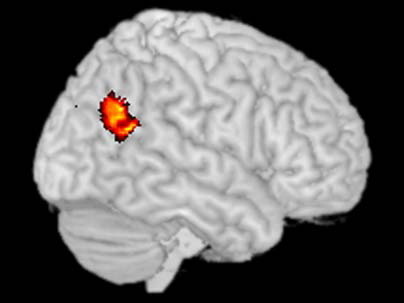

En concreto, la técnica utilizada por Saxe y su equipo de investigadores ha sido la del registro de imágenes por resonancia magnética funcional (fMRI. Esta técnica permite medir la respuesta hemodinámica -o de los flujos sanguíneos del cerebro-, relacionada con la actividad neuronal, es decir, que hace posible saber qué regiones del cerebro se activan cuando la gente está pensando en ciertas cosas.

Gracias a la fMRI, Saxe identificó que existe un área concreta del cerebro que se enciende cuando tratamos de entender porqué los otros actúan como actúan. Este área sería la denominada unión temporoparietal, que es el lugar en el que se encuentran el lóbulo temporal y el lóbulo parietal del cerebro.

Se sabe que esta región cerebral juega un papel fundamental en los procesos de distinción entre el yo y los demás. Por otro lado, daños en ella se han relacionado con la aparición de episodios de experiencias extracorporales. Estas experiencias también han podido inducirse, de manera artificial, mediante la aplicación de estímulos eléctricos a la unión temporoparietal.